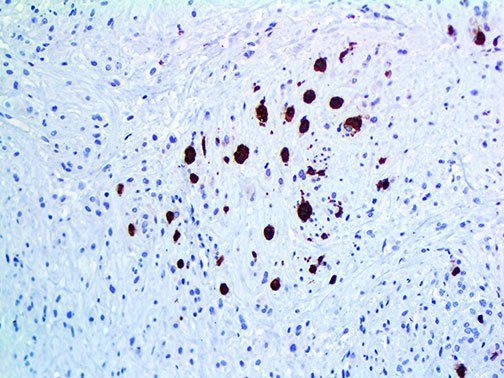

It is the ICU physician who is most likely to witness one of the deadliest manifestations of the abnormal immunological response, the cytokine storm syndrome (CSS). This response is also referred to by some as the cytokine release syndrome (CRS). CSS is characterized by continuous activation and expansion of macrophage and lymphocyte populations, which secrete large amounts of cytokines, causing the cytokine storm. This massive cytokine release is akin to hemophagocytic lymphohistiocytosis (HLH) disease, a syndrome characterized by initial unchecked and persistent activation of cytotoxic T lymphocytes and NK cells.

Clinical and laboratory manifestations of HLH include fever, enlarged liver and/or spleen, neurologic dysfunction, coagulopathy, liver dysfunction, cytopenias (i.e., low levels of erythrocytes, leukocytes, and/or platelets), hypertriglyceridemia, hyperferritinemia, hemophagocytosis, and eventually diminished NK cell activity as the immune system becomes progressively paralyzed. HLH can be familial (primary HLH) or secondary to another disease process (sHLH), such as rheumatic disease, in which it is referred to as macrophage activation syndrome (MAS, characterized by elevated ferritin).